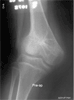

At 6 months post last surgery, patient can ambulate independently without any pain in the knee. Patient claims no limitation from activities of daily living. Range of motion of the knee is progressively improving. Presently it is 0 to 100 degrees.